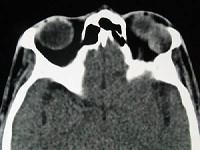

问题 女,36岁,左眼眶外上部可触及一无痛性包块有两年,眼球向内下方突出,CT检查如图,最可能诊断为 ( )

选项 A、淋巴瘤 B、淋巴瘤样增生 C、泪腺恶性上皮性肿瘤 D、炎性假瘤 E、泪腺良性混合瘤

答案 E